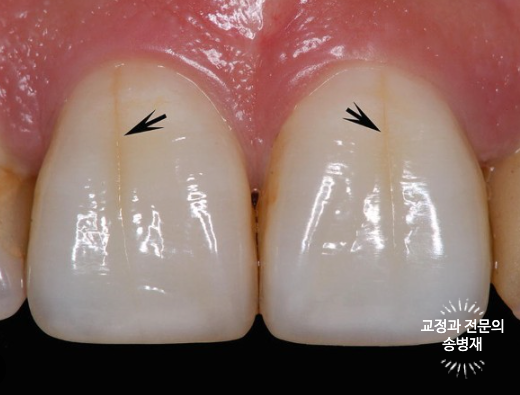

위에서 빨간 화살표로 표시한 실금이 잘 보이시나요?

치아에서 보이는 실금은 craze line이라고 부르며, 치아 표면 약 0.1mm 내의 야주 얕은 깊이의 실금입니다.

이러한 실금은 훨씬 더 깊이 금이 간 치아파절(crack line)과 구별됩니다.